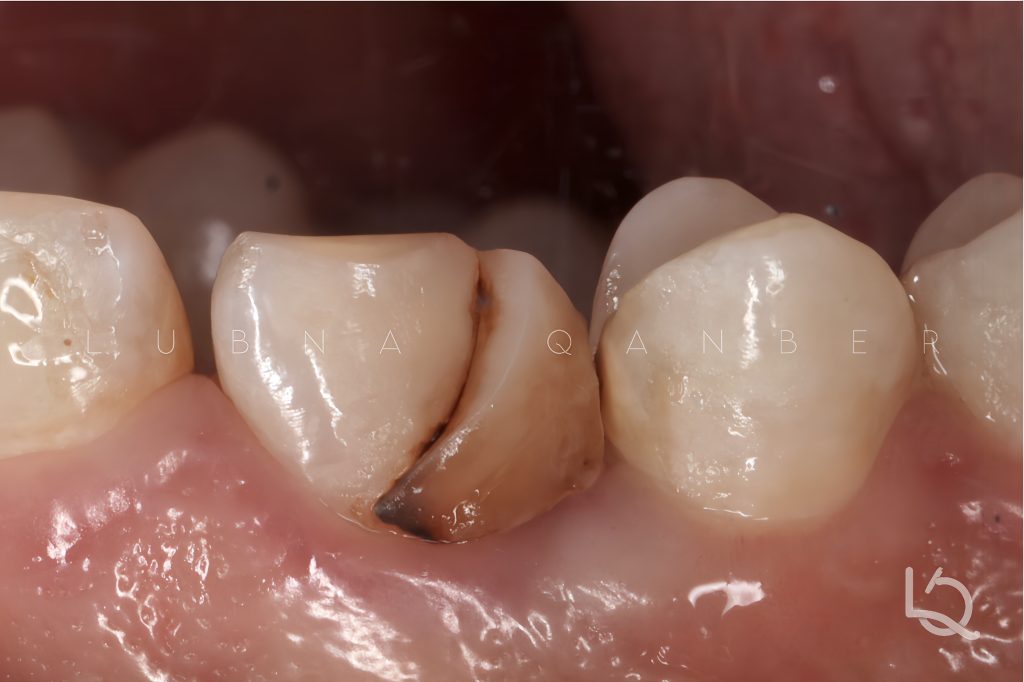

In addition, proximal caries were identified on both the mesial and distal surfaces of the adjacent premolars (#24, #25).

The procedure began with removal of the old composite and isolation of the operative field. Following endodontic retreatment of the canine.

Upon evaluating the interproximal space which was relatively wide, I observed that restoring the distal cavity of the canine alone would not help in creating a properly contoured contact point. Therefore, I decided to simultaneously restore the mesial side of the first premolar (#24), to better control the emergence profile and establish an ideal proximal contact with the canine.